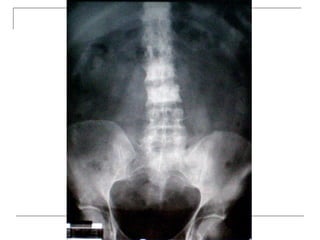

• 25.

Lateral -fracture/wedging -kyphosis -spondylolisthesis  Oblique -spondylolysis (SCOTTIE DOG)